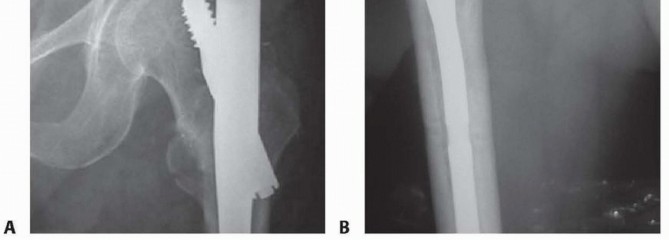

feed rate. This means that the guidewires and reamers bend and can be misdirected with excessive axial force during drilling. 5. For single-device and integrated screw femoral head fixation, the surgeon should use a center-center position for the large lag screw. 6. For two-device femoral head fixation (reconstruction), the inferior screw is placed first along the medial calcar of the femoral neck; this will ensure room for the proximal screw. Distal locking 1. Distal locking is usually recommended with a dynamic single screw for short and long nails. Two distal interlocking screws are recommended for comminuted or segmental fractures. ## POSTOPERATIVE CARE 400 AP and lateral radiographs of the final construct should be obtained in the surgical suite before recovering the patient to assess the construct and ensure stability. If there are adjustments to be made, these are best made while the patient is still under anesthesia. Radiographs should reveal the entire fracture region, including the entire implant construct. Patients are mobilized to a chair upright position the day after the operative procedure. Ambulation with supervision is allowed, with weight bearing as tolerated with a walker or crutches and emphasis on heel-strike and upright balance exercises. 10 Multiple trauma or patients with other complications may have delayed ambulation, but it should begin as soon as possible to minimize secondary complications. Patients are reevaluated with an examination and radiographs at 2 weeks and then monthly thereafter until fracture healing is documented and the patients have maximized ambulatory capabilities, usually by 6 months after the injury. The surgeon should emphasize good nutrition and hip abductor exercises bilaterally. Patients must be counseled to report any increased swelling or respiratory distress as an emergency because of the high risk of thromboembolic disease. ## OUTCOMES Union of these fractures is high (more than 95%) with cephalomedullary nail techniques.

### FIG 7 • Nail failures. A. Proximal screw cutout. B. Distraction nonunion with spiral blade nail construct. Functional recovery is poor in many patients, however, with more than 60% of patients failing to recover their preinjury level of function. 12 Mortality within the first year in patients older than 55 years is 20% to 30%. Many patients sustain progressive collapse of the hip into varus and shortening of the leg with the current generation of sliding hip screw fixation. 13 ## COMPLICATIONS

Loss of construct stability is one of the most common complications.

It is manifested by collapse of the screw and varus migration of the femoral head construct, with final cutout failure in the worst cases. This occurs to a small degree in all cases, as the sliding impaction was designed to minimize catastrophic cutout.

A center-center position of single-screw devices minimizes cutout. 4

Nail cutout is a much more serious complication, involving loss of fixation of the nail component in the proximal femur or periprosthetic femoral fracture with short nails; this will result in reoperation with locking construct plates or 95-degree blade plates, exchange for longer nails, or even prosthetic replacement in severe cases ( FIG 7A). If a lateral trochanteric portal was used, prepare for trochanteric accessory fixation

if arthroplasty is required. 6

Nonunion, although rare (1% in older patients), is usually treated with total hip replacement and grafting and implant revision in young patients ( FIG 7B).